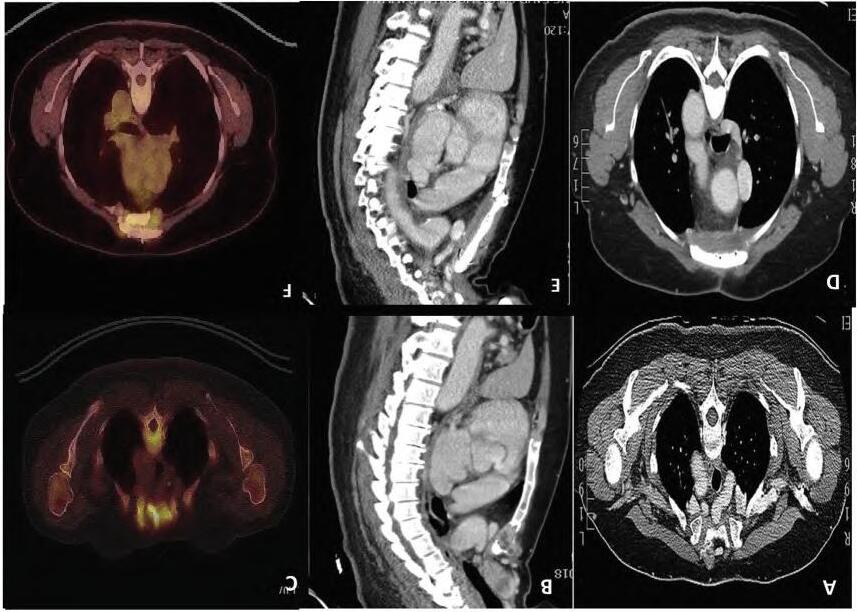

Fig.2.10 (A,B)Computedtomography(CT)scanofthethorax,axialandsagittalviews,showingmanubrialmetastasis.(C)Preoperativepositronemission tomography(PET)scanofthethoraxshowingmetastasis.(D,E)PostoperativeCTscanshowingreconstructionofthemanubriumsterniiwithanMMSplate.(F) PETscanofthethoraxafter2yearsshowingthemethylmethacrylatemarlexmeshplate(MMS)plateingoodpositionandnorecurrence.(FromChaudhryIUH, CheemaA,AqeelC,etal.Radicalresectionandimprovisedmanubriosternalreconstructiontechniqueforsolitarymanubriosternalmetastasisfrom papillarythyroidcancer. IntJSurgCaseRep.2020;76:278 281[Fig.2].ISSN2210-2612, https://doi.org/10.1016/j.ijscr.2020.09.201, http://www.sciencedirect.com/science/article/pii/S2210261220308749.)